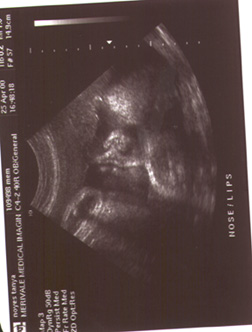

April 25, 2000 ~ Today was an exciting day! We went for my ultrasound in Ottawa. We were amazed at the show, it was about a half hour long and the details you can see on a baby this age are amazing! We saw his eyes moving, his lips moving, his aorta, he had a full bladder, right and left brain, etc, etc. It was really neat. The technician estimated his size to be 7 pounds 3 oz. at 37 wks 3 days. She also said though, that the estimate could be high or low by a pound or more, so I guess you really can't know! We got a picture of his face, close up. Here it is below:0)